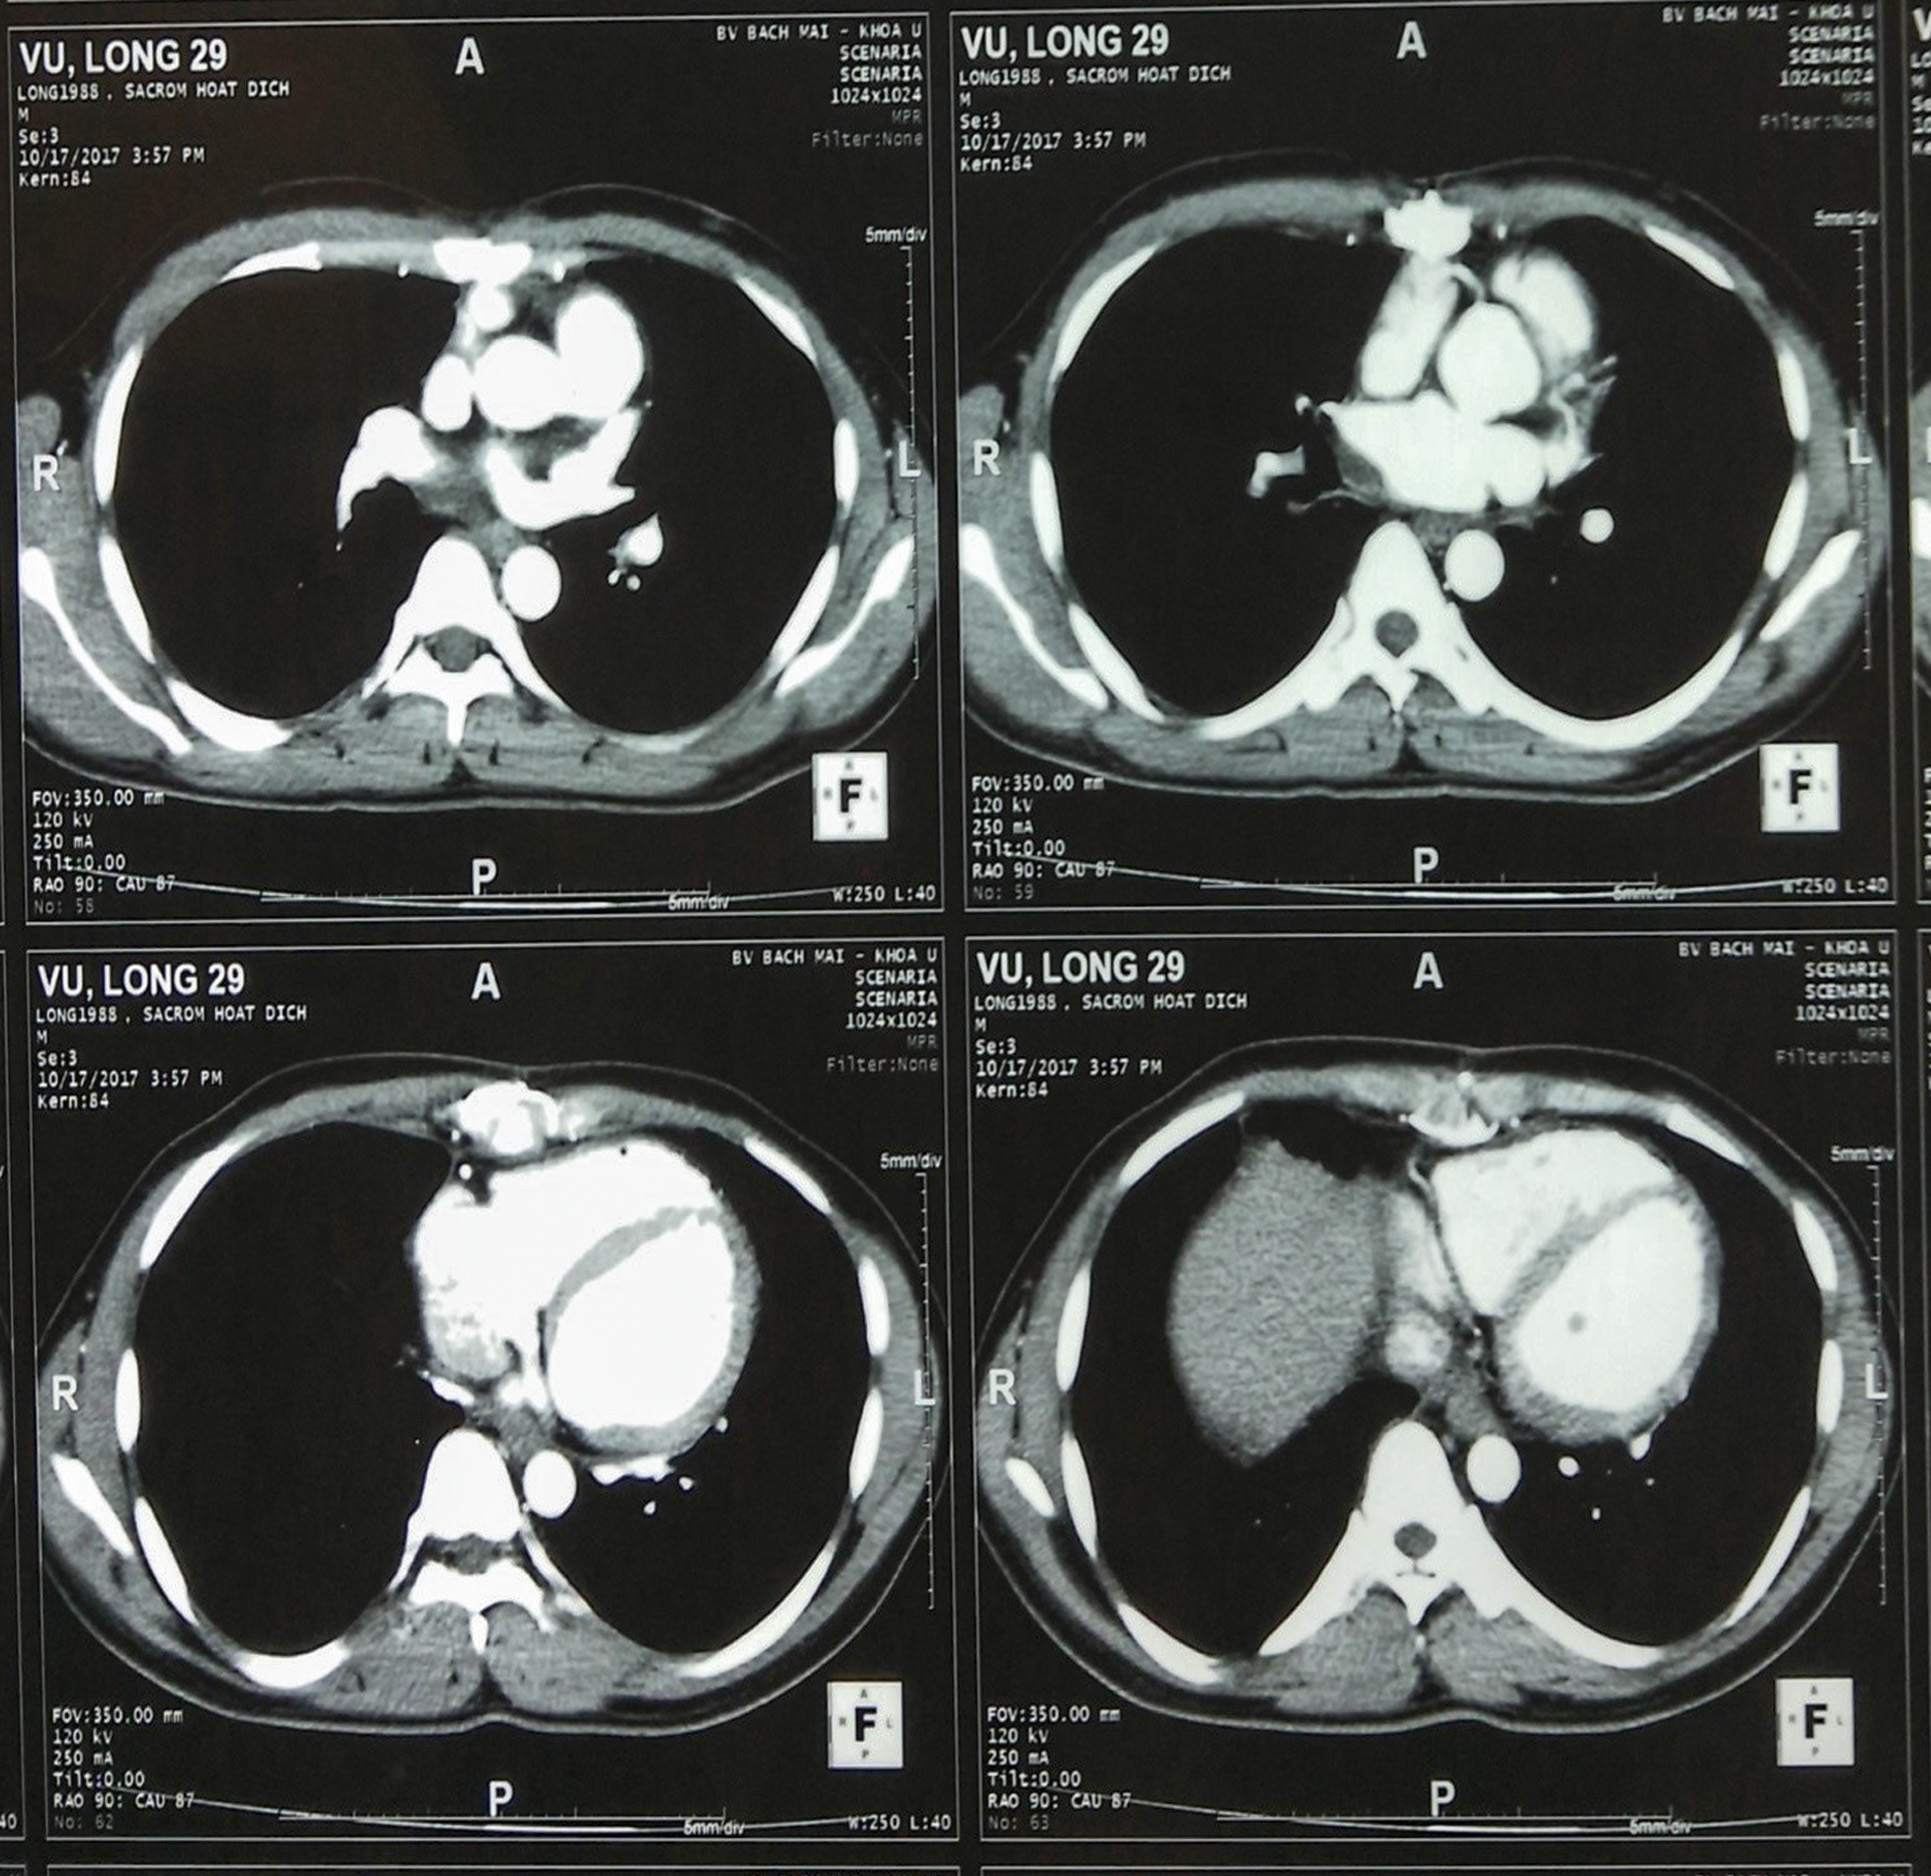

Hình 1: Hình ảnh chụp cắt lớp vi tính (CT) lồng ngực có khối u trung thất còn lại sau phẫu thuật xâm lấn nhĩ phải và trung thất, dịch màng phổi phải

Bệnh sử: Trước vào viện một tháng, bệnh nhân xuất hiện tức ngực khó thở tăng dần, kèm theo gầy sút suy kiệt, da xanh niêm mạc nhợt. Bệnh nhân được khám ở một bệnh viện tỉnh Hải Dương và được chụp cắt lớp tính phát hiện khối u trung thất giữa xâm lấn nhĩ phải.

Bệnh nhân khó thở nhiều, không nằm được đầu thấp, sau đó được chuyển đến Viện Tim mạch, Bệnh viện Bạch Mai. Tại đây, bệnh nhân được mổ lấy u, đánh giá trong mổ khối u trung thất lớn xâm lấn nhĩ phải màng tim và các mạch máu lớn, được phẫu thuật lấy phần lớn khối u, sau mổ một phần khối u vẫn còn trên đại thể (khối u không lấy hết được).

Sau 7 ngày hậu phẫu, bệnh nhân được rút hết ống dẫn lưu và chuyển sang Trung Tâm Y học hạt nhân và Ung bướu – Bệnh viện Bạch Mai trong tình trạng gầy suy kệt, thiếu máu, đỡ khó thở, vết mổ liền tốt. Bệnh nhân tiếp tục được truyền máu, nuôi dưỡng.

Sau mổ kết quả mô bệnh học là sarcoma bao hoạt dịch.